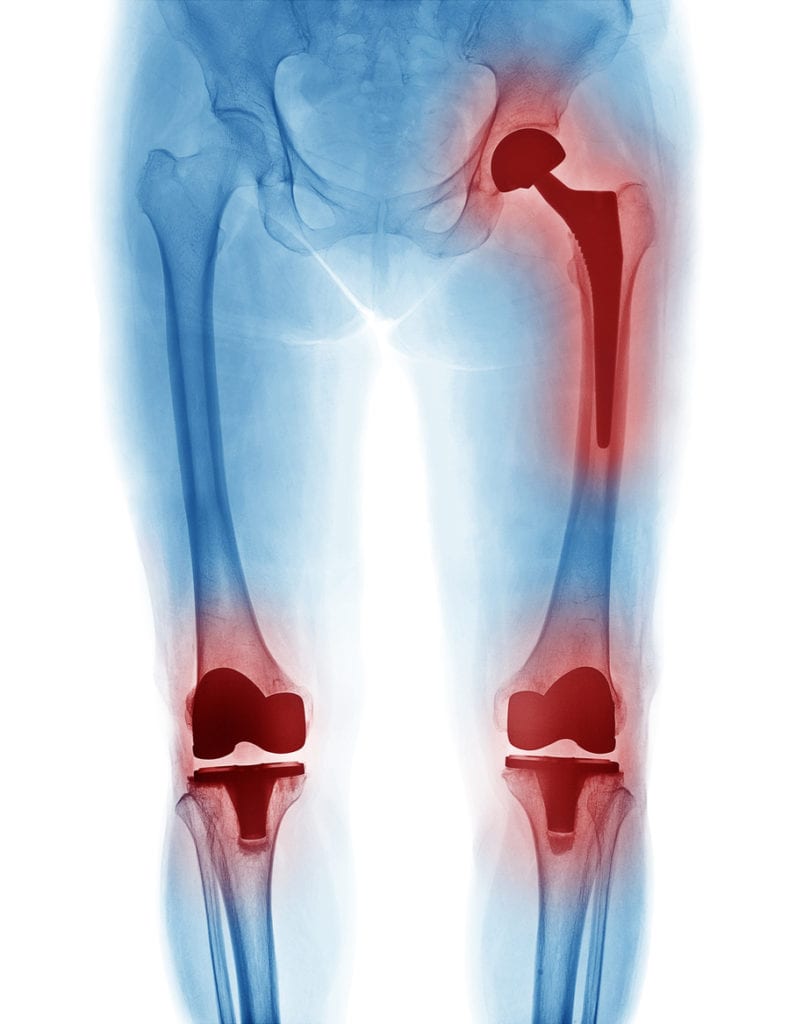

More than 600,000 knee replacement surgeries are performed every year in the United States. This surgery aims to relieve painful and disabling symptoms in the knee – usually due to arthritis – and to restore knee function.

The prostheses used in knee arthroplasties are made of highly durable materials, such as ceramic and titanium. They can last 20 years or even longer. Talk to your surgeon about how to increase the longevity of your knee prosthesis.